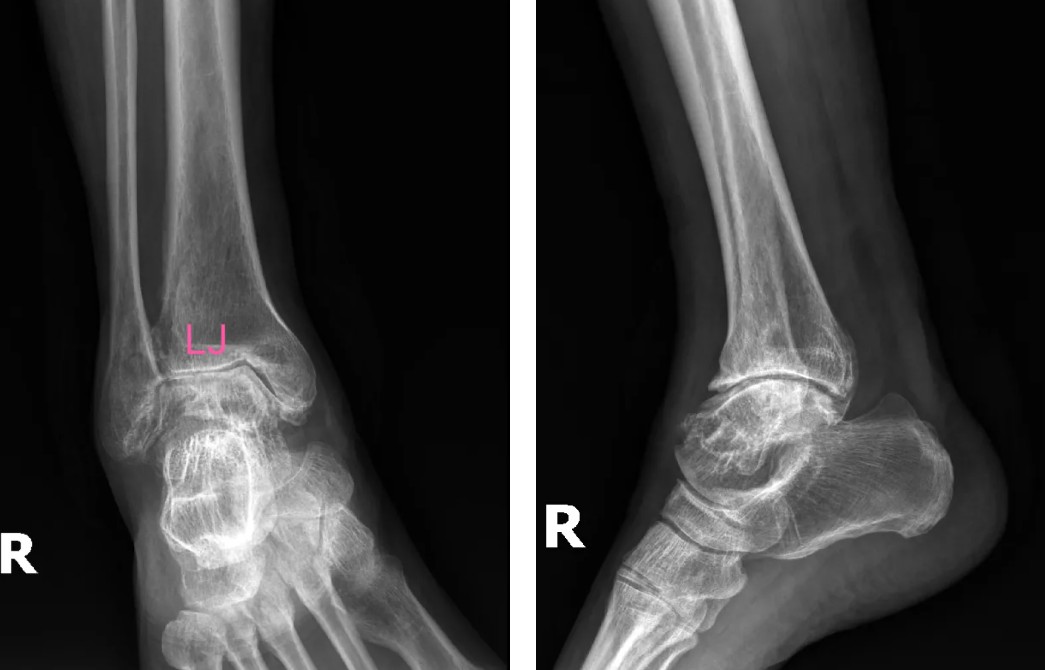

術(shù)前影像

患者吳先生(66歲)雙踝關(guān)節(jié)疼痛、活動(dòng)受限長達(dá)10余年,保守治療無效后,關(guān)節(jié)逐漸畸形腫脹,連正常走路都成了奢望。廣安醫(yī)院副院長、關(guān)節(jié)科主任羅軍副主任醫(yī)師團(tuán)隊(duì)經(jīng)全面評(píng)估,決定采用3D打印定制化人工全踝關(guān)節(jié)置換術(shù)。